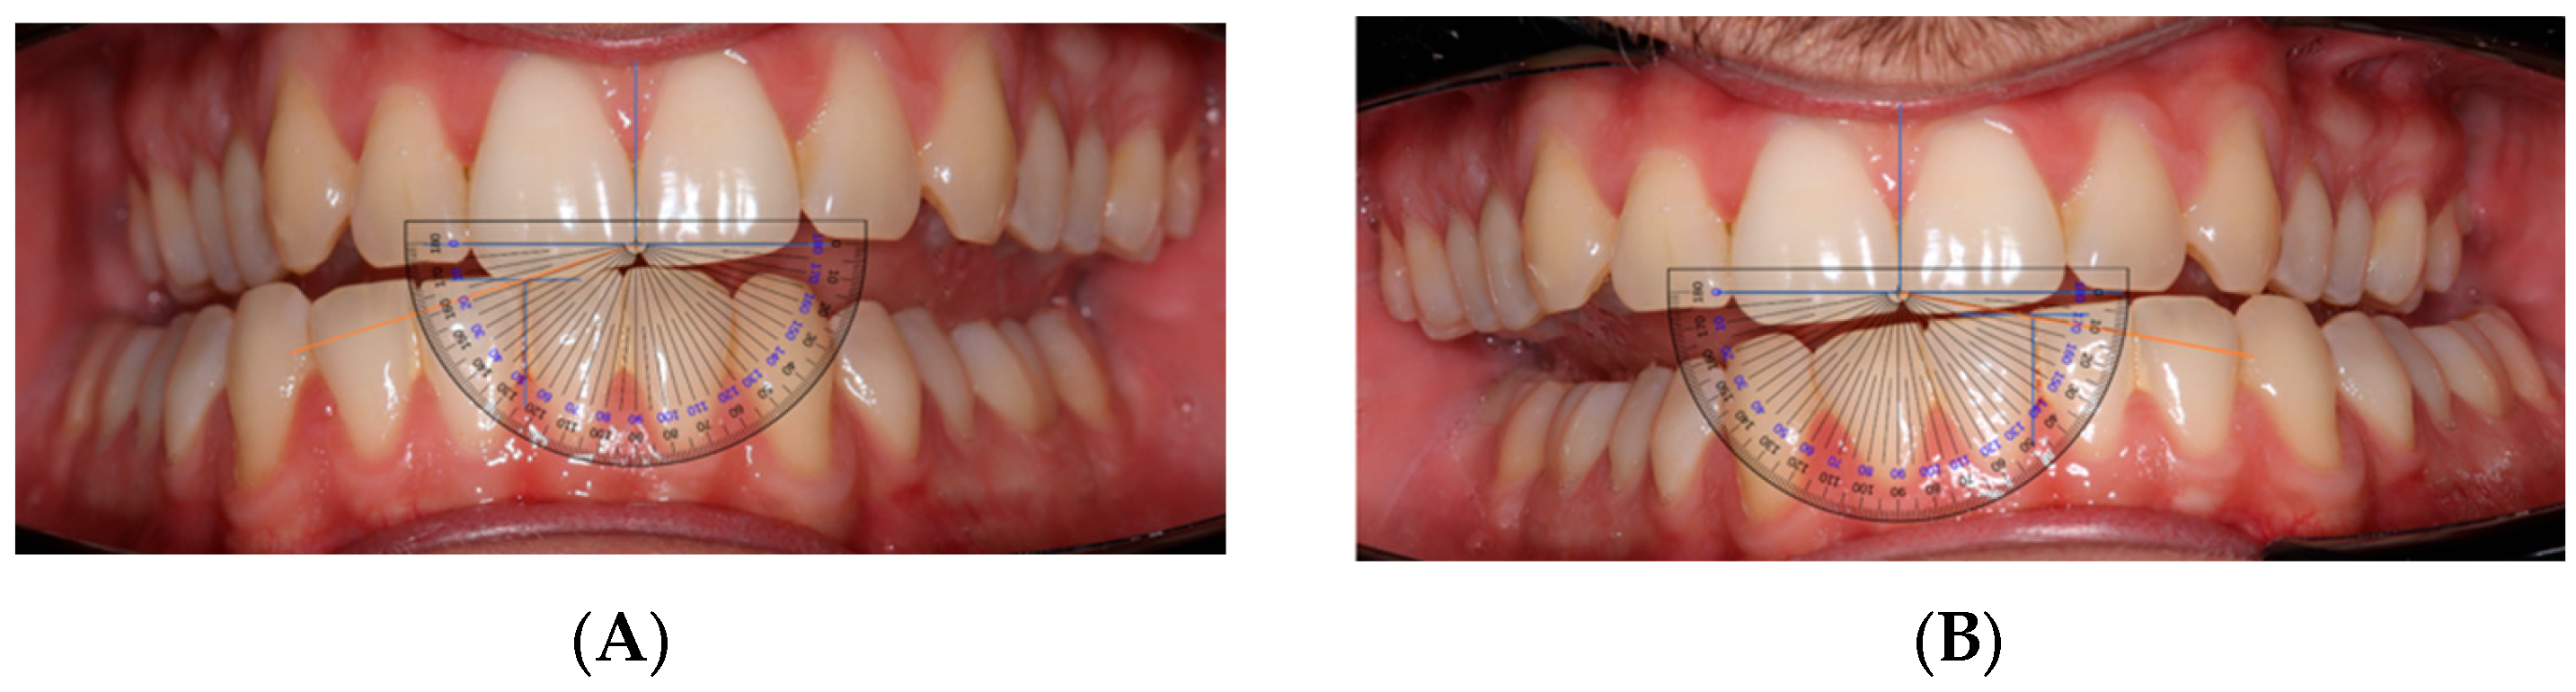

All intraoral photographs were taken by the same trained orthodontic postgraduate operator using standardized cheek retractors to ensure full visibility of occlusal planes. A Canon 250D camera with a 100 mm Sigma macro lens was used. Images were saved in JPG format, imported into Microsoft PowerPoint, and magnified at a uniform scale before tracing reference axes. AFMP angles were then measured by overlaying a digital protractor (PNG format) on the traced axes to minimize measurement error.

• AFMP Measurement: Horizontal and vertical reference axes were traced on images using PowerPoint. Angles were then measured using a transparent angle protractor overlay (Figure 1). Reference axes were defined using the maxillary incisal edge line and the mandibular interincisal point; vertical axes corresponded to the dental midlines. This procedure was selected as a pragmatic, low-cost alternative to specialized software. It should be regarded as a preliminary clinical tool rather than a standardized protocol.

Figure 1. (A): Right-side AFMP measured using a protractor overlay. (B): Left-side AFMP measured using a protractor overlay.